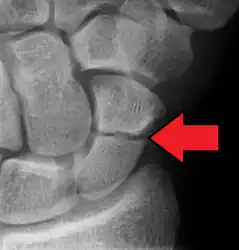

| An X-ray showing a fracture through the waist of the scaphoid | |